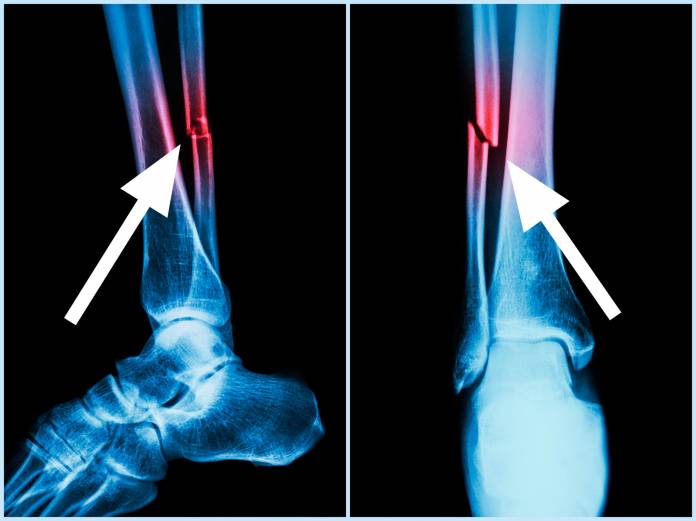

Ein gebrochenes Wadenbein lässt sich durch einige Untersuchungen feststellen. Normalerweise wird zuerst ein Untersuchungsgespräch, die Anamnese, abgehalten. Der Patient erklärt den Unfallhergang und berichtet dem Arzt über seine Beschwerden und gegebenenfalls über Vorerkrankungen. Daraufhin erfolgt die körperliche Untersuchung. Dabei kann der Arzt am Sprunggelenk auch Beweglichkeitstests durchführen. Der Bruch im Wadenbein wird in der Regel auf dem Röntgenbild sichtbar. Dort ist auch der Bruchverlauf erkennbar. Unter Umständen können noch Untersuchungen wie eine Computertomographie (CT) oder eine Kernspintomographie (MRT) angebracht sein.